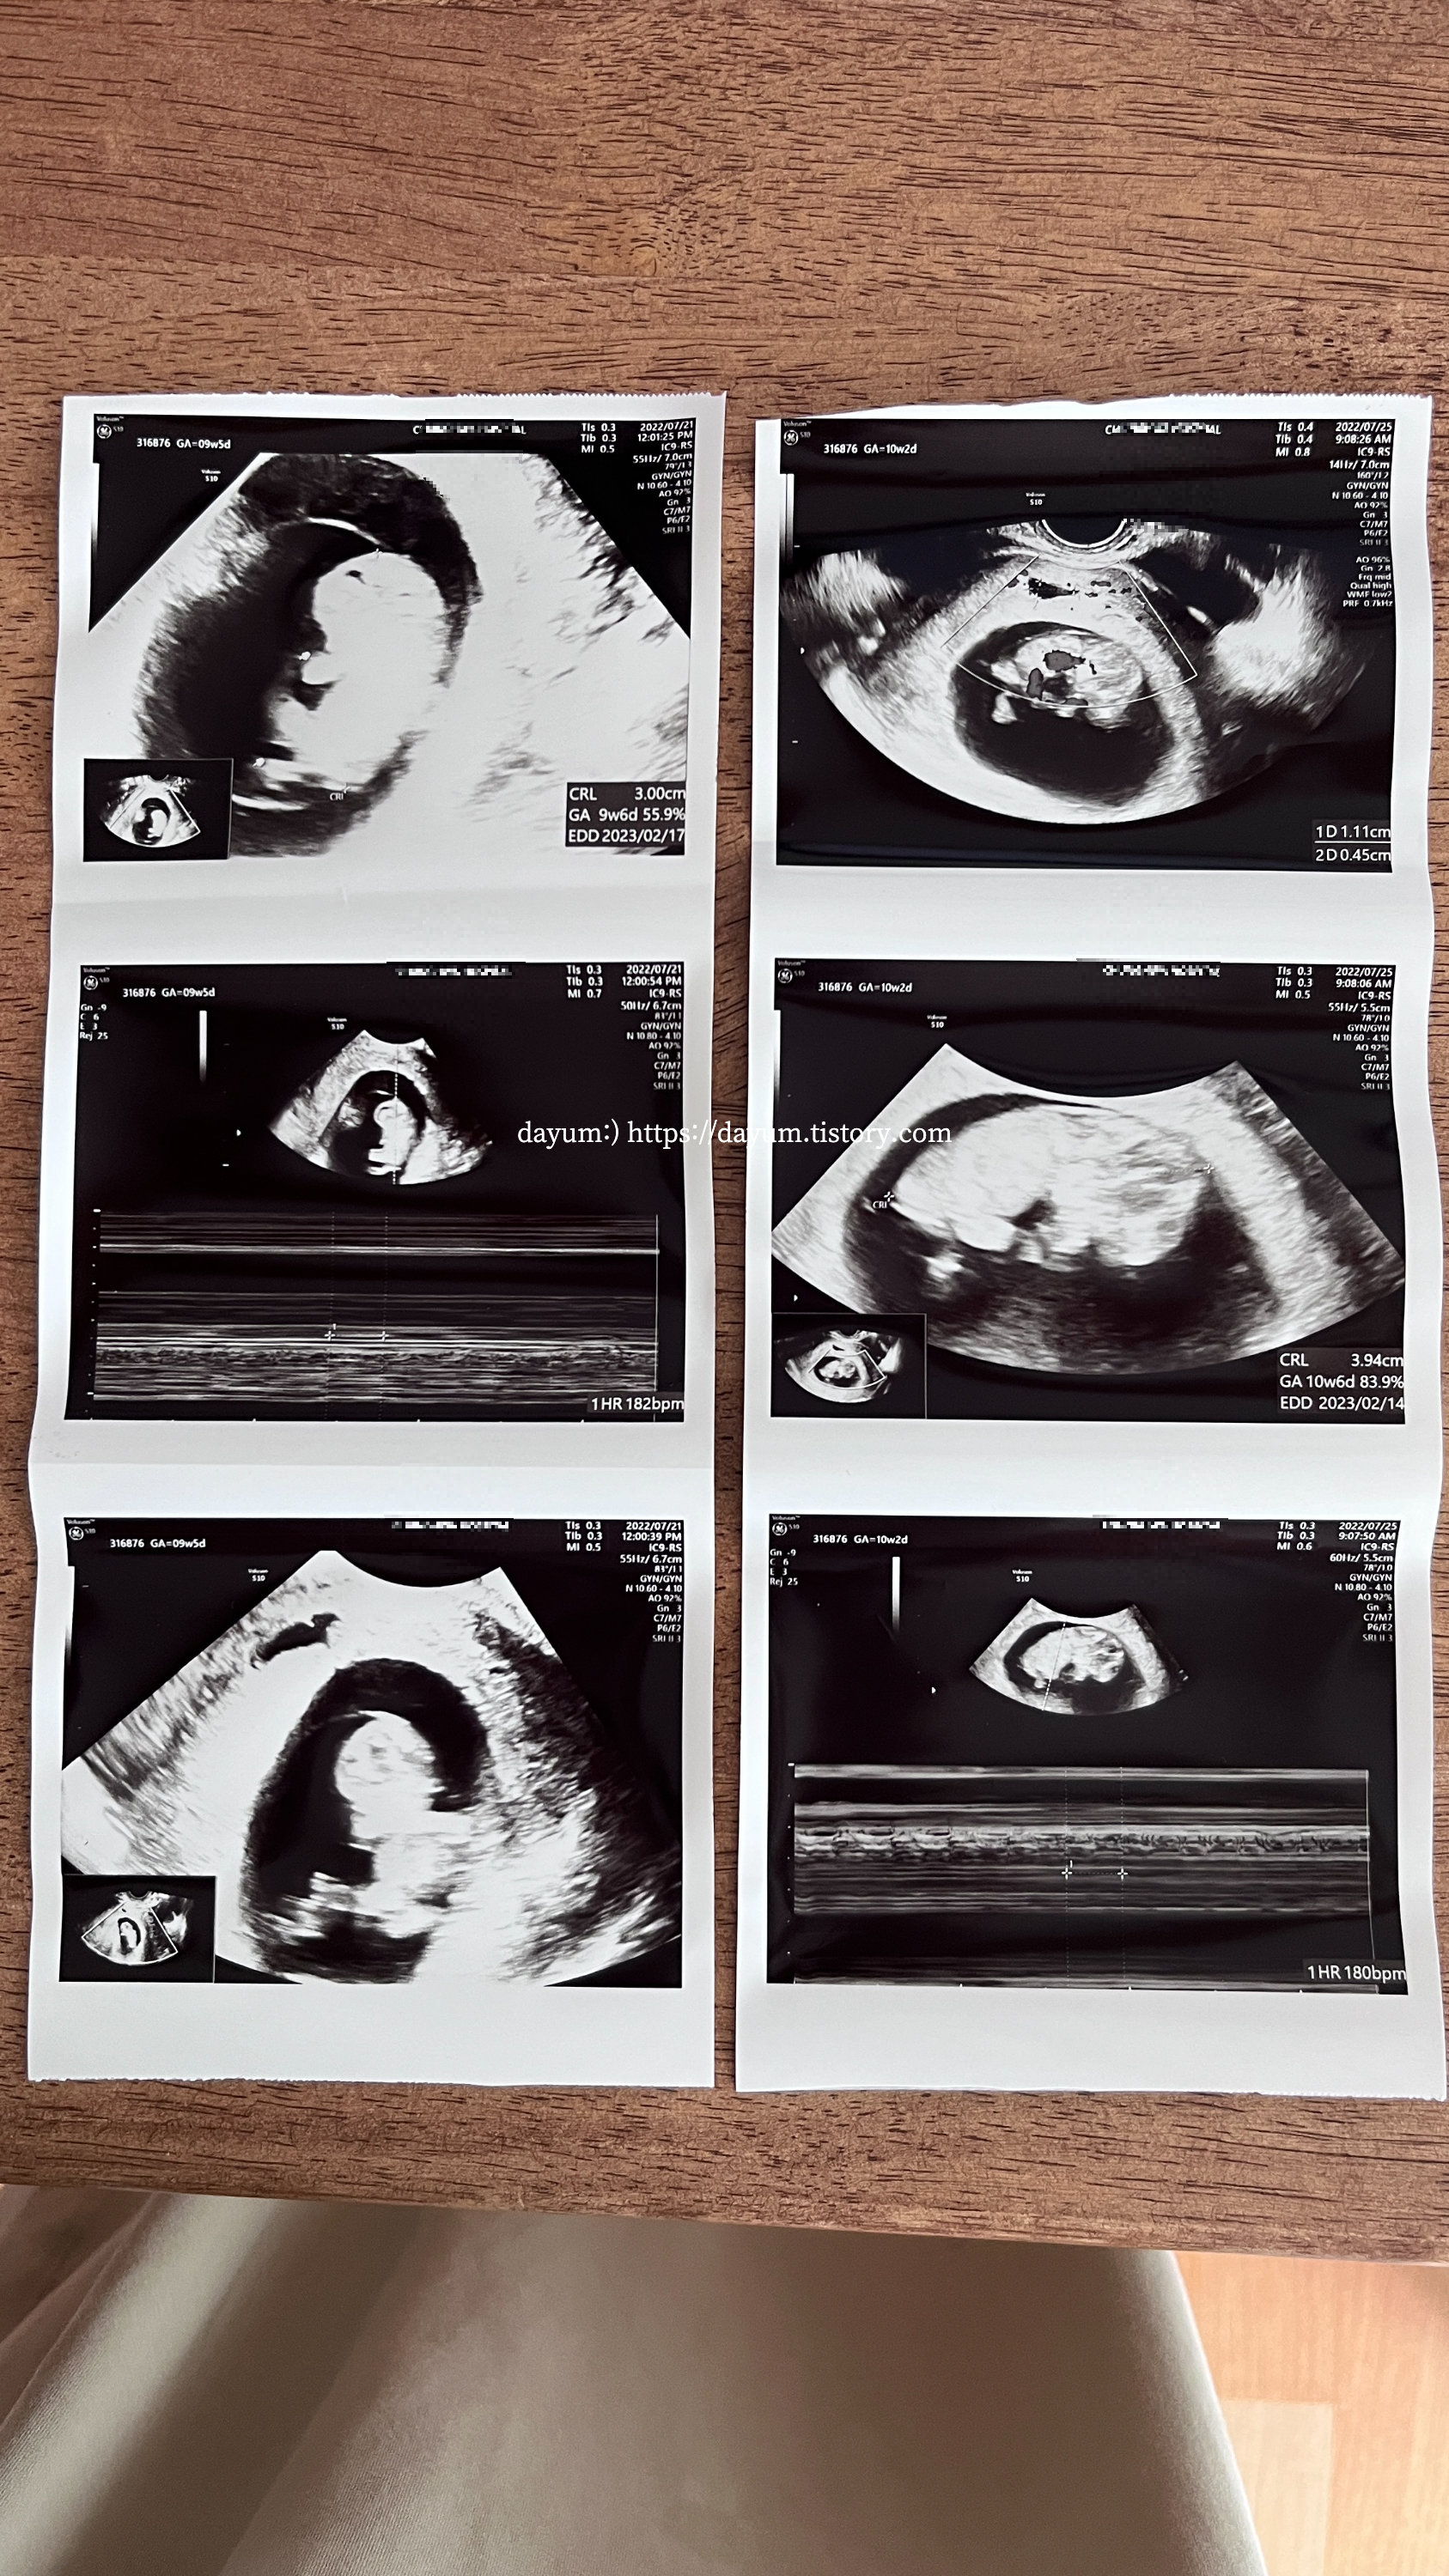

원래대로라면 12주에 1차 기형아검사를 하러 가는거였는데 또 피가 비쳐서 아침 일찍 병원을 다녀왔다.

초음파를 보니 전에 있던 작은 피고임이 사라지고 새로운 피고임이 생겼다고 한다.

그 사이에 94mm나 자라 있었다.

그리고 10주 5일 되는 날, 또 피가 나왔다. 그런데 이번에는 붉은색에 가까운 갈색피였다.